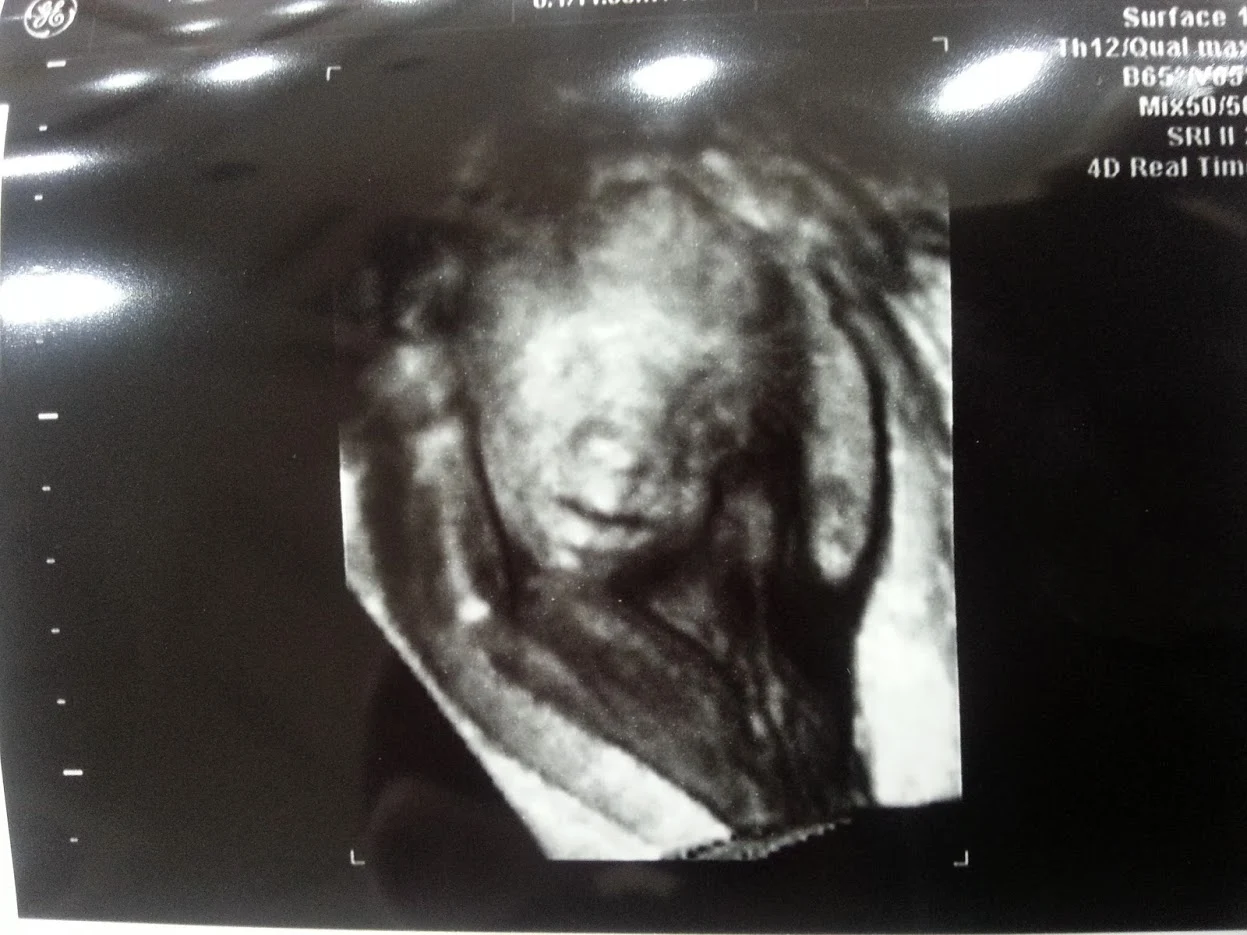

아내의 임신

결혼 후 아이가 들어섰다. 아내는 일을 하고 있었다. 배는 불러왔고 남편의 따뜻한 돌봄이 필요한 시기였다. 변해가는 몸에 대한 두려움과 출산에 대한 불안함을 함께 이겨나갈 남편이 있어야 할 시기가 바로 임신 기간이다.